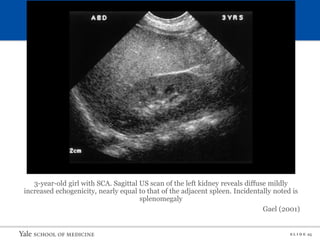

Workup

• Urinalysis with microscopy

• Assess proteinuria/albuminuria

• Renal function panel

• Renal ultrasound

– Early - > large, variable echogenicity

– Shrink with CKD

– Papillary necrosis

• Increased echogenicity of the inner medulla

• In more advanced cases, a filling defect in the area of the

medullary tip can be seen

3-year-old girl with SCA. Sagittal US scan of the left kidney reveals diffuse mildly

increased echogenicity, nearly equal to that of the adjacent spleen. Incidentally noted is

splenomegaly

Gael (2001)